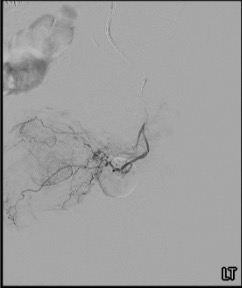

Selective DSA & Prostatic Artery Identification

Angiographic Anatomy on Pelvic Arteriogram

On ipsilateral oblique selective IIA arteriography, the pelvic arterial branches are best identified using the PROVISO system. The prostatic artery arises most commonly from the anterior division, courses inferomedially toward the prostate, and gives rise to anteromedial and posterolateral intraprostatic branches. Ipsilateral oblique views (20–50 degrees) separate overlapping vessels, while caudal angulation (10–20 degrees) helps delineate bladder branches from prostatic feeders. Venous phase on the prostatic arteriogram confirms complete parenchymal perfusion.